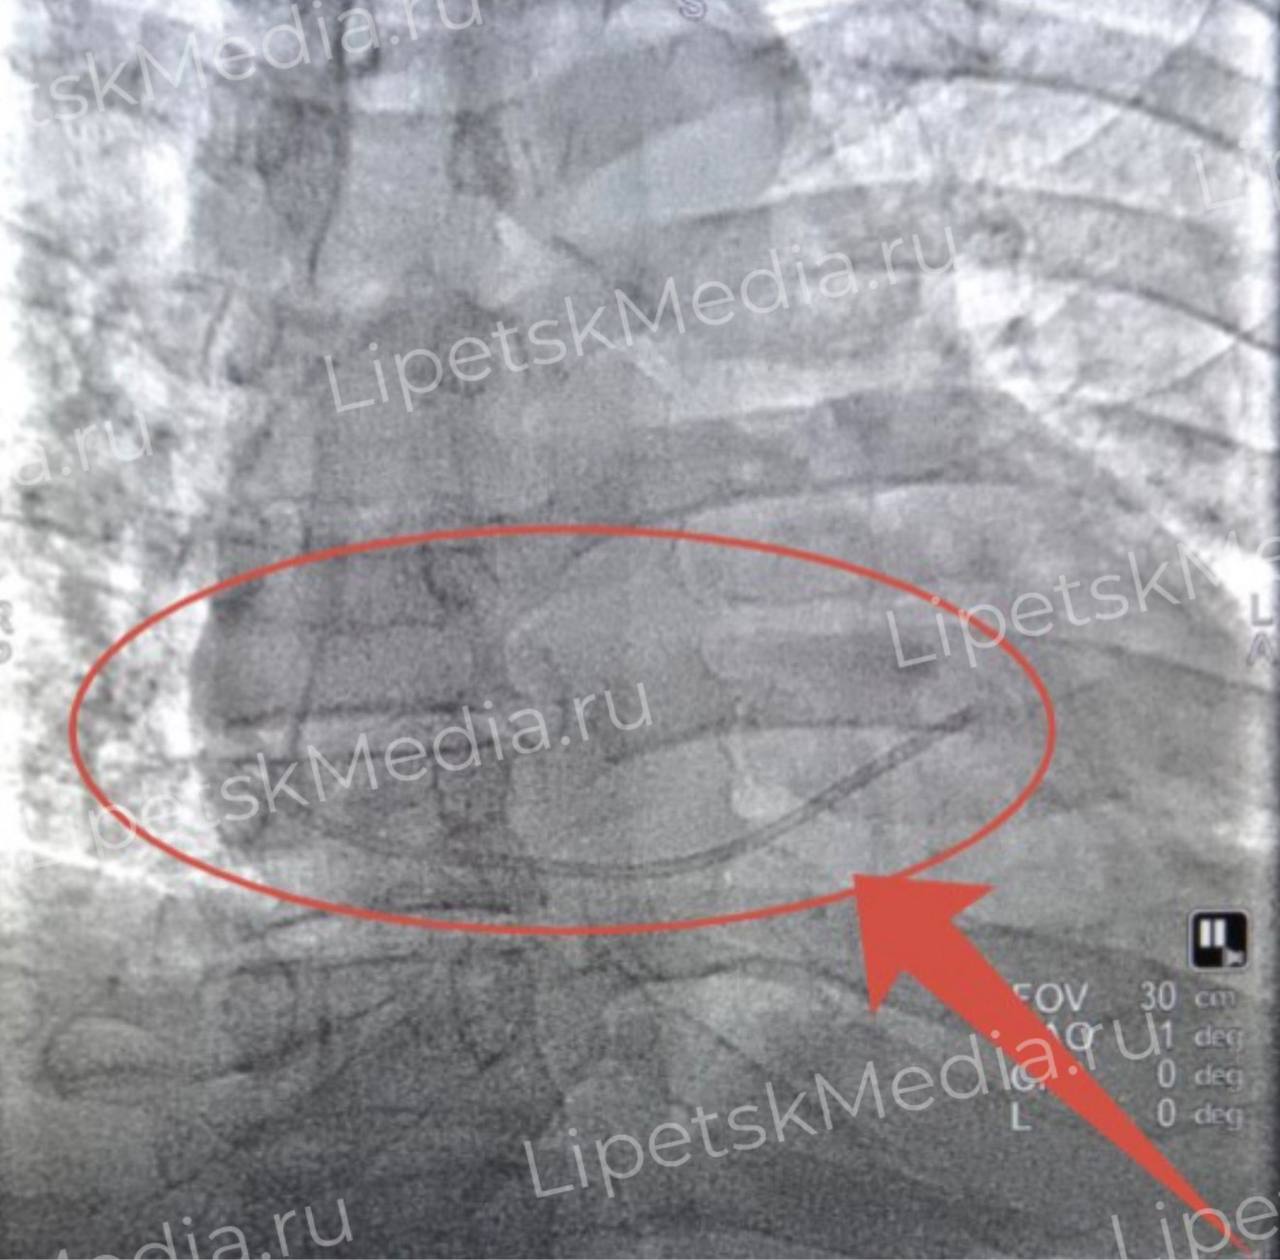

Пациента экстренно доставили в областную больницу и через сосудистый доступ извлекли обломок катетера из правого желудочка сердца, сообщают медики.